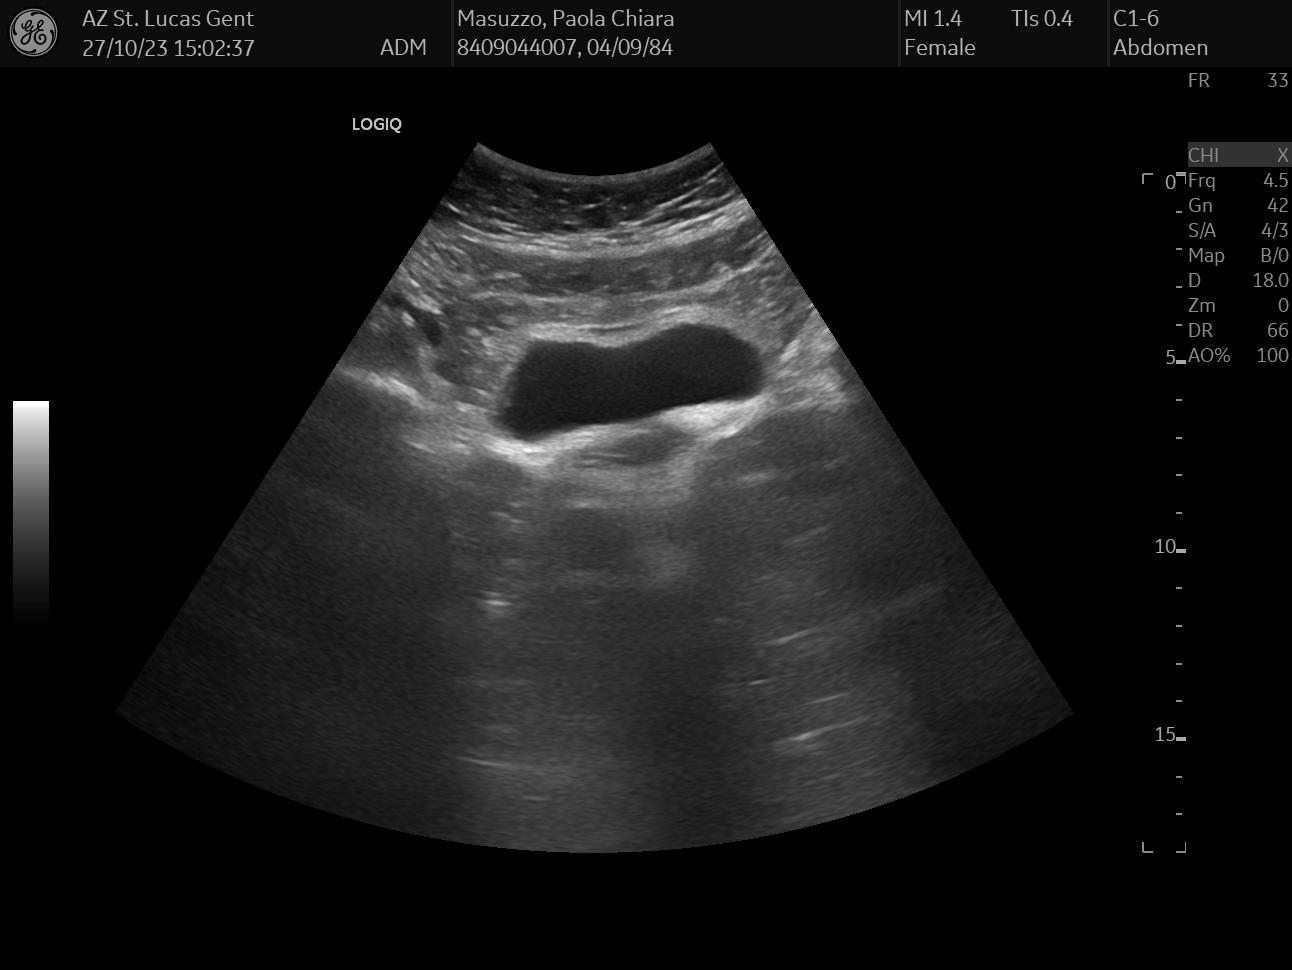

On the same day, I also had an abdomen ultrasound of my liver, gallbladder, and bile duct, which together can paint a pretty accurate status of your hepatic health - or lack thereof.

Like with any ultrasound exam carried over by a physician, the visit was pretty painless and I got the results on the spot: everything looked pretty normal. For this exam, I selected random data: I chose 3 images that looked the funniest to me, but I honestly have no idea what they mean.